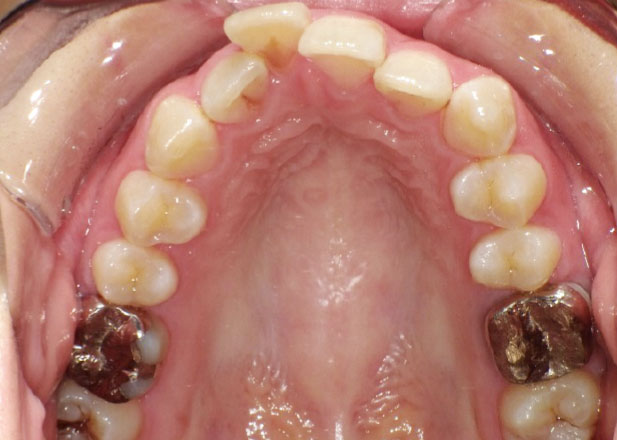

治療前

マウスピース矯正 マウスピース矯正 マウスピース矯正

口腔内写真